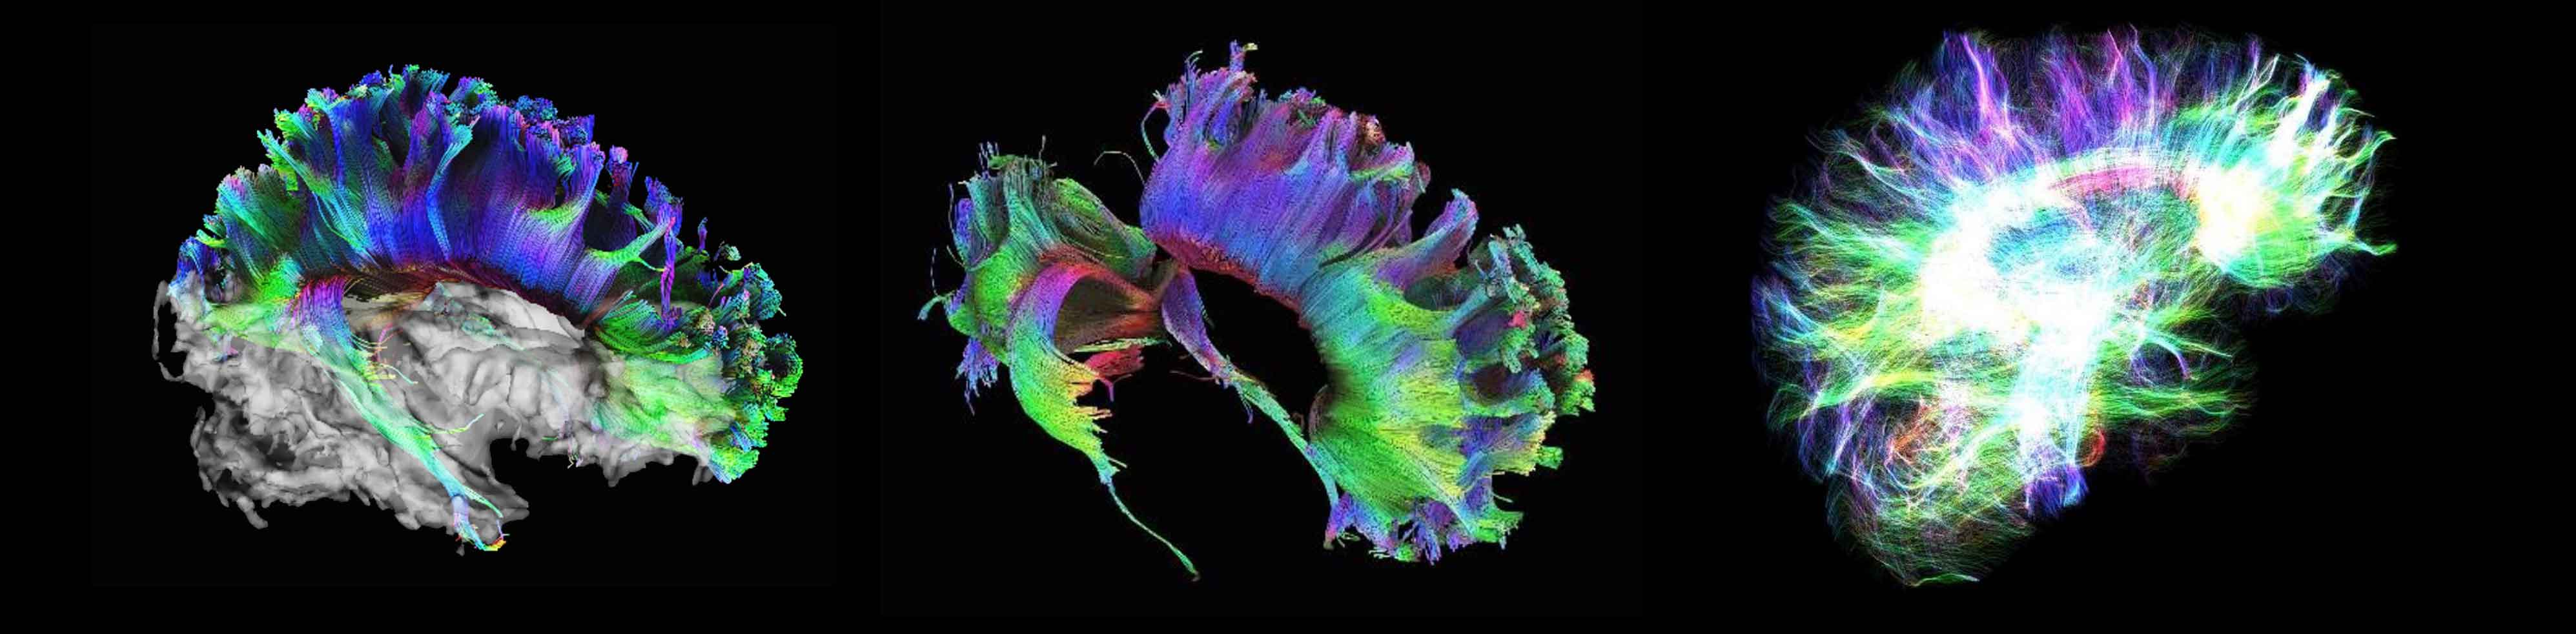

High angular diffusion imaging

The neuroscience team used 257 different directions, 23 b-values and a maximum b-value of 4000 s/mm² to collect the data below in a total scan time of 11 minutes. The higher number of gradient directions combined with multiple b-values not only allows for improved fiber tracking in these examples, but also enhances the analysis of intra-voxel incoherent motion (IVIM) and diffusion kurtosis (DK) effects in one single measurement.

High angular diffusion imaging

The neuroscience team used 257 different directions, 23 b-values and a maximum b-value of 4000 s/mm² to collect the data below in a total scan time of 11 minutes. The higher number of gradient directions combined with multiple b-values not only allows for improved fiber tracking in these examples, but also enhances the analysis of intra-voxel incoherent motion (IVIM) and diffusion kurtosis (DK) effects in one single measurement.